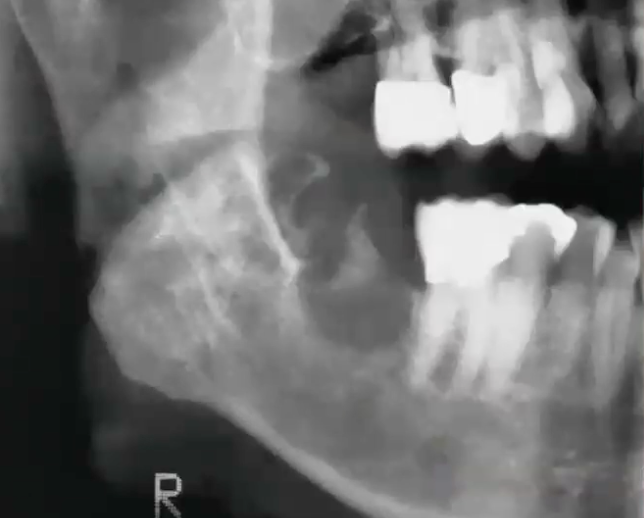

<p>CBCT showed bone destruction. What is the diagnosis?</p>

CBCT showed bone destruction. What is the diagnosis?

Adenoid cystic carcinoma